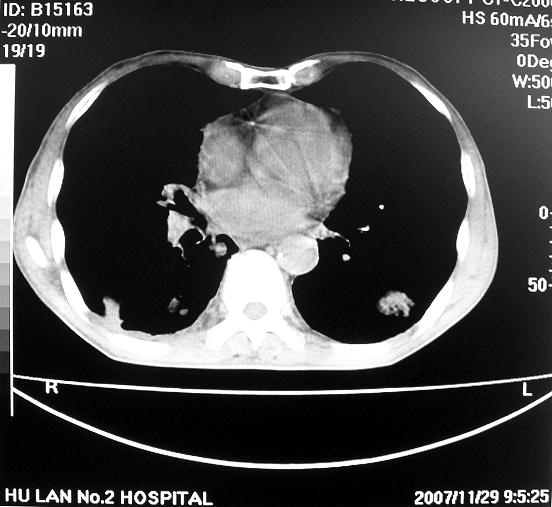

男63岁胸痛来诊

右下肺周围性肺ca并双肺及右侧胸膜转移。[emb6]

右肺病灶前缘不平整,略呈分叶状,其后方胸膜下脂线消失且似有向胸壁浸犯,左下肺球形灶内可见不规则空洞影,余双肺内可见多枚结节影,结合病史支持考虑肺癌肺内转移胸膜转移,便双肺后部病灶倒也是结核好发区域,建议穿刺活检

右下肺周围性肺ca并双肺及右侧胸膜转移。

右下肺周围性肺ca并双肺及右侧胸膜转移。单看病变像炎性假瘤。

右下肺癌伴双肺及胸膜转移。

[quote]以下是引用余辉在2007-12-2 20:29:00的发言:[br]右肺病灶前缘不平整,略呈分叶状,其后方胸膜下脂线消失且似有向胸壁浸犯,左下肺球形灶内可见不规则空洞影,余双肺内可见多枚结节影,结合病史支持考虑肺癌肺内转移胸膜转移。

左肺病灶内可见空泡征及典型的胸膜牵拉征,不排除原发周围型肺癌的可能.